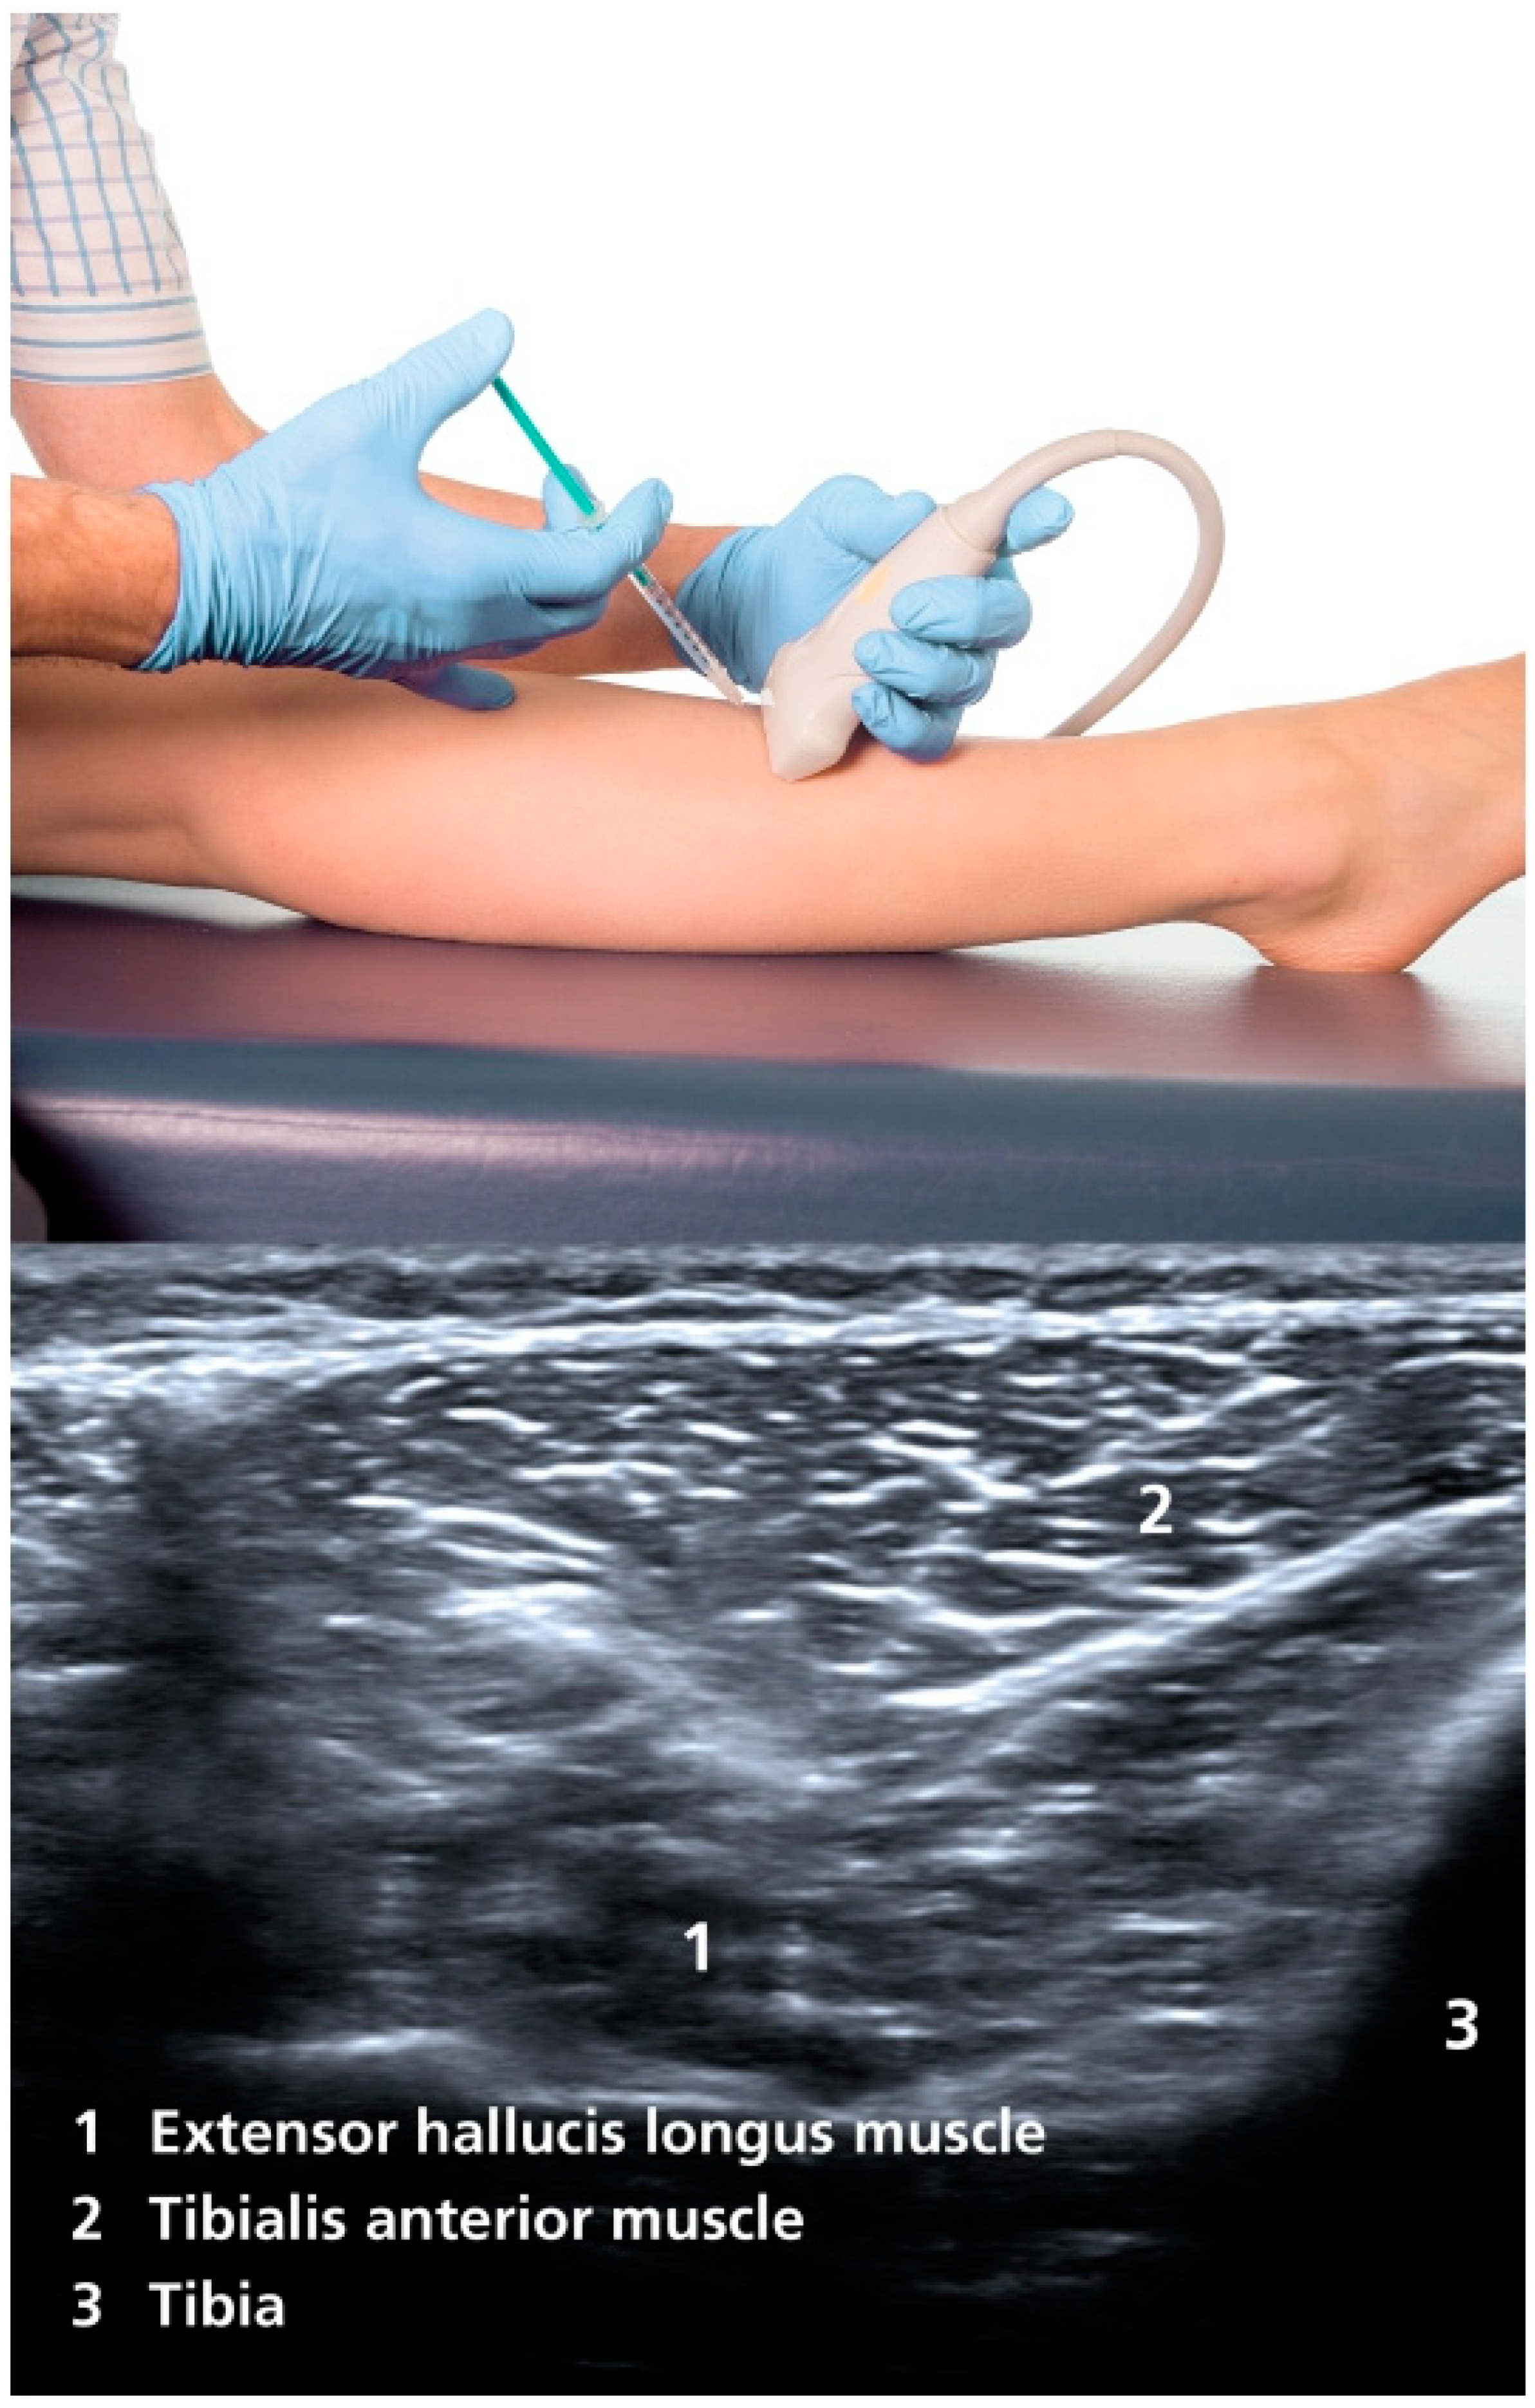

By injecting BoNT into the extensor hallucis longus muscle, a reduction of the dorsiflexion of the hallux in striatal toe can be achieved. The injection should always be carried out under ultrasound control to avoid incorrect injection. The extensor hallucis longus muscle originates from the middle half of the fibula and the adjacent interosseous membrane, extends deeply between the anterior tibial muscle and the extensor digitorum longus muscle, and terminates at a tendon that attaches to the base of the terminal phalanx of the hallux [20]. The injection is made between the distal and middle third of the lower leg, along the lateral edge of the tibia [21]. At this height, the muscle can be visualized dorsal to the anterior tibial muscle and lateral to the tibia with ultrasound (Figure 1). This is often difficult to distinguish from the extensor digitorum longus muscle; therefore, it is helpful to activate the muscle (dorsiflexion of the hallux) in order to be able to better demarcate it. The usual dosage is initially 20 to 40 U of incobotulinum toxin A or onabotulinum toxin A, or 80 to 140 U of abobotulinum toxin A, although the dose can be titrated higher, depending on the therapeutic response (we usually start with a lower dose). The injection should be repeated and adjusted every three to four months. It should be noted that there is no official approval for the treatment of striatal toe with BoNT and that the therapy is a case-by-case decision.

Figure 1. Injection site and ultrasound imaging of the extensor hallucis longus muscle [21].